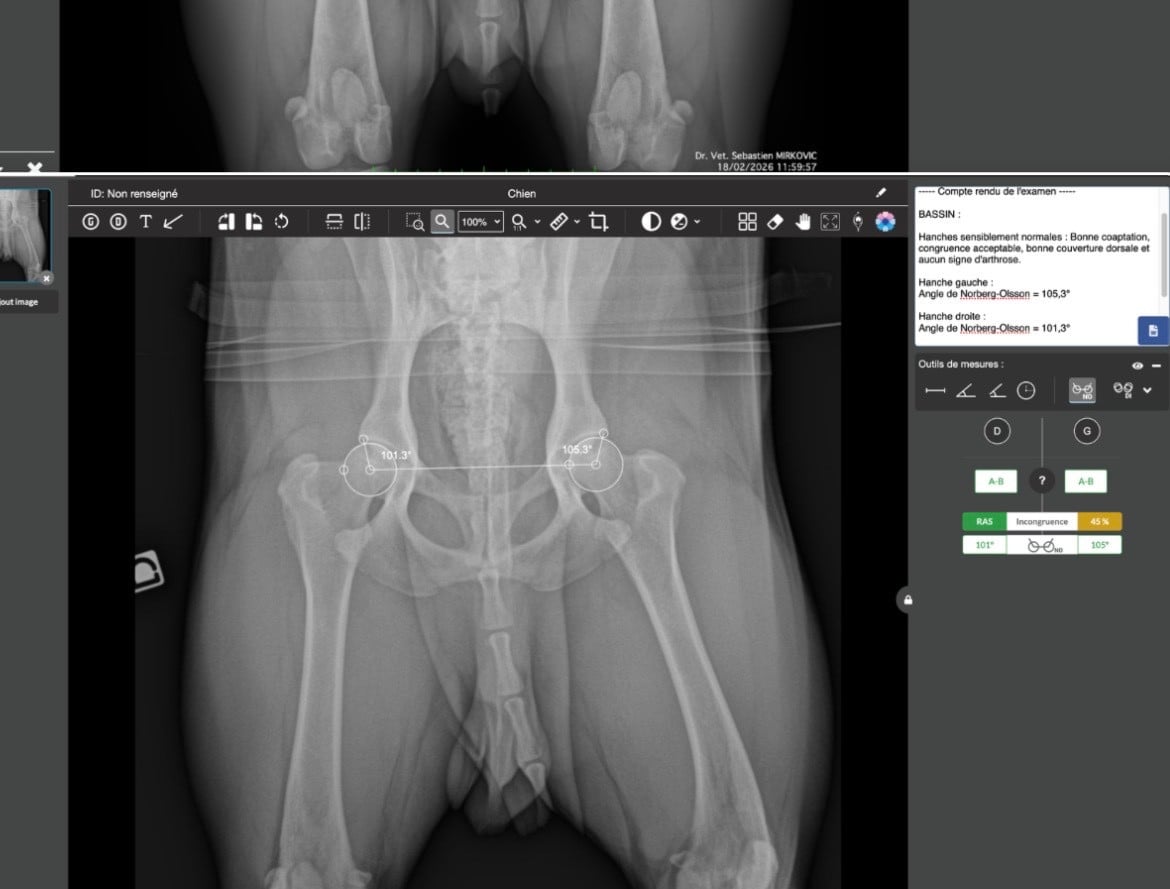

Hanche - A/BCoudes - 0Prcd 1-1 / Eic 1-1 / Hnpk 1-2/ kit scc Clear - Clear